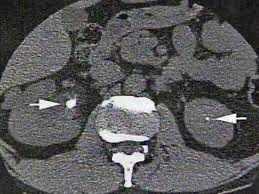

Le metodiche diagnostiche utilizzate per l’identificazione delle condizioni sovracitate comprendono l’ecografia (metodica poco costosa ma operatore-dipendente), la TC (Figura 2) e l’urografia

EV. Occasionalmente sono necessarie la cistouretrografia minzionale, l’uretrografia retrograda o la cistoscopia. Nelle donne con cistite sintomatica o con cistiti asintomatiche ricorrenti, non sono necessarie indagini urologiche di routine, perché questi reperti non influenzano la terapia. La nefrolitiasi è molto frequente, specie in età adulta e si classifica per la formazione di calcoli organici (Figura 3) (per malformazioni delle vie urinarie) e funzionali (per squilibrio metabolico). Nello specifico, per i pazienti di età pari o superiore a 65 anni, le condizioni correlate con formazione di calcoli includono la ridotta mobilità, la carenza di assunzione di liquidi, le infezioni croniche, la menopausa per diminuzione dei livelli di estrogeni endogeni, la riduzione della densità